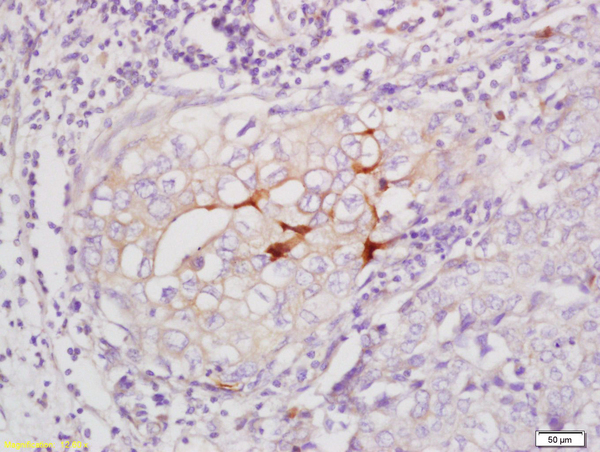

Supportive validation

- Submitted by

- Bioss (provider)

- Main image

- Experimental details

- Formalin-fixed and paraffin embedded human breast carcinoma labeled with Anti-Phospho-Beta-Catenin(Ser33/37) Polyclonal Antibody, Unconjugated (bs-3084R) at 1:200 followed by conjugation to the secondary antibody and DAB staining

- Sample type

- Human

- Other comments

- Breast